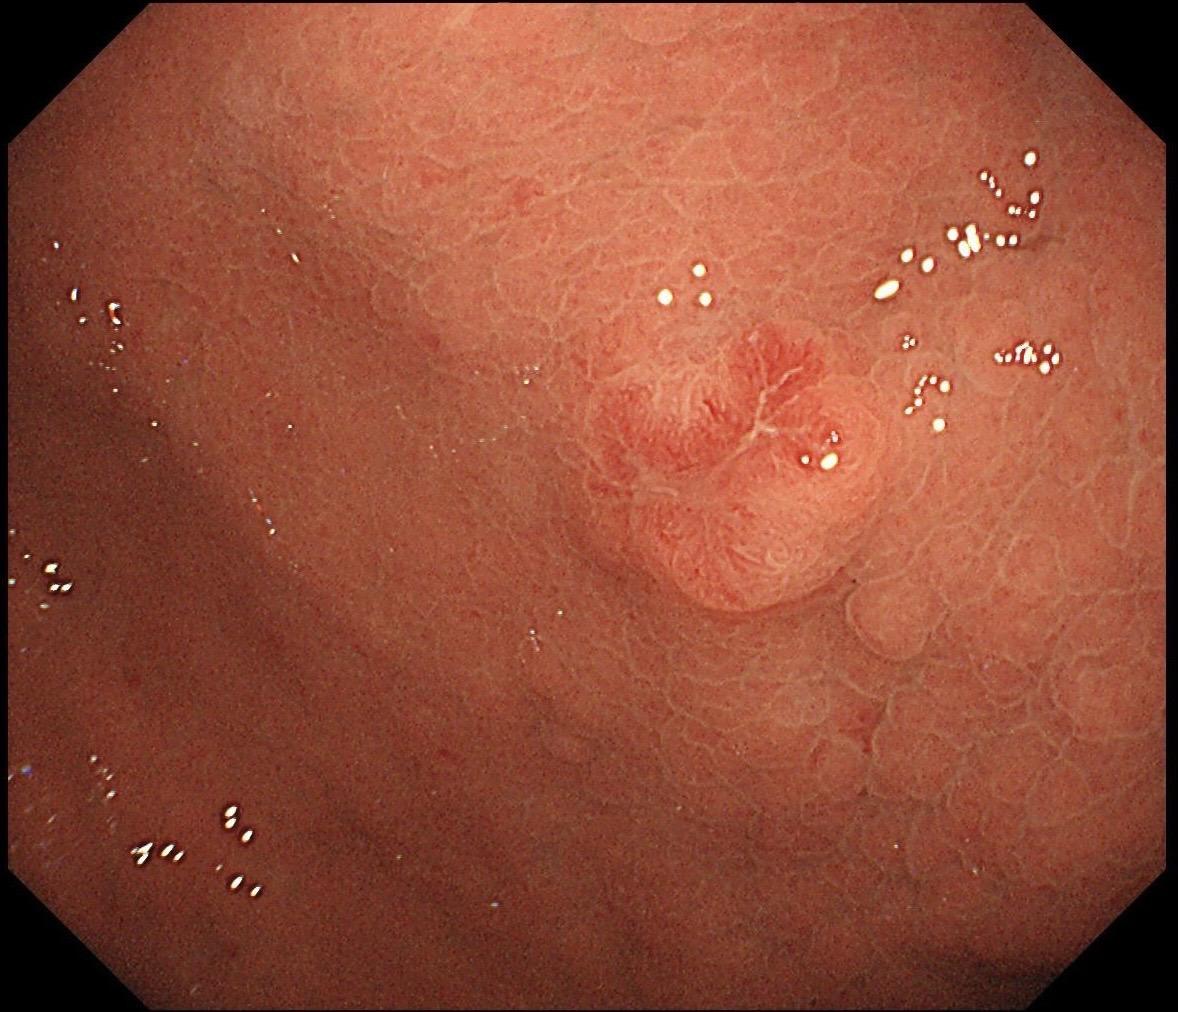

男,70岁,胃底体双发病变。看图猜猜病理呢……尤其胃底这个小的~凹陷性病变,当中央结构观察欠清时,边缘的异常微血管往往有提示作用,哪怕是局部。两处都考虑早期病变,拟ESD微创治疗。